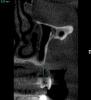

SergeyAL Опубликовано 29 мая, 2013 Поделиться Опубликовано 29 мая, 2013 коллеги столкнулся с такой ситуацией 5 лет назад были установлены поднадкостничные имплантаты имени д-ра Раада пациенту пообещали, что 5 лет они точно прослужат на срезах КТ видно, что прослужили, но в некоторых местах албвеолярного отростка не осталось после их службы)) послу удаления их остались сплошные рубцы, удалять которые смысла не импло, т.к. они были спаяны со Шнайдеровой мембраной или то, что от нее осталось последние фотографии через 4 месяца после их удаления, слизистая представляет собой сплошной рубец. коллеги, поделитесь, какую тактику применяете при выраженных рубцовых деформациях, когда впереди еще костная пластика, имплантация и т.д. Ссылка на комментарий

SergeyAL Опубликовано 30 мая, 2013 Автор Поделиться Опубликовано 30 мая, 2013 коллега, каких синусов, толщина в области синуса менее 3-х мм, а расстояние от костной ткани до предполагаемой реставрации 10-15мм!!!!! Ссылка на комментарий

SergeyAL Опубликовано 30 мая, 2013 Автор Поделиться Опубликовано 30 мая, 2013 там выраженная редукция тканей по ширине,даже в в области синуса около 3 мм Ссылка на комментарий

SergeyAL Опубликовано 30 мая, 2013 Автор Поделиться Опубликовано 30 мая, 2013 там не везде есть костная пластинка, местами рубцы из ротовой полости спаяны со Шнайдеровой мембраной или что там от нее осталось Ссылка на комментарий